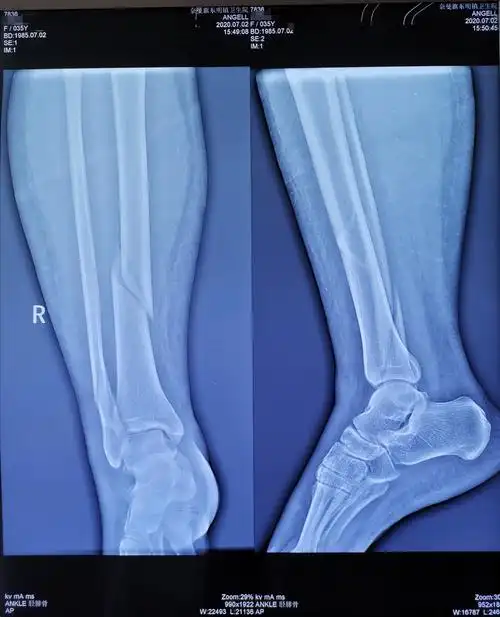

通辽市第二人民医院骨科为35岁女性右胫腓骨下段骨折患者行胫骨闭合